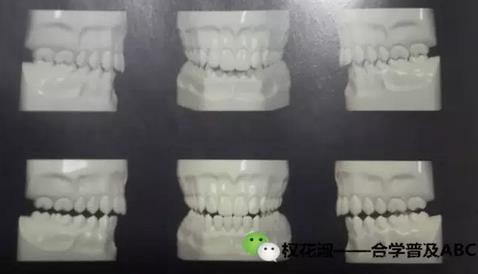

看這張圖的三個接觸關系。有一個誤區(qū),認為最后一種接觸關系是咀嚼效率最高的,在調(diào)磨牙齒時努力想做到牙齒面面接觸。當然現(xiàn)在,很多醫(yī)生非常清楚,第三種接觸是我們最不愿看到的一種接觸關系,第一種和第二種現(xiàn)在是有爭議的。我們也會在后期專題探討。至少大家要知道,臨床上的多種接觸方式,我們希望的是點式接觸,而不是面式接觸。

那么關于合,大家首先要在腦海中有一個概念,單組牙齒、每一組上下牙齒是怎樣的接觸關系,當然這里邊還隱含著我們上下牙齒具體的接觸方式,首先我們要掌握理想狀態(tài)的接觸關系,這里做一點引申:我們的牙齒的接觸是一對一還是一對二?我們先思考以后再探討的。

大家看這兩張圖,有什么區(qū)別,做一個比較。

以上給大家是一個靜態(tài)的咬合關系,只是一個正面的圖,不要在腦海里只想到正面,還要考慮側面,還要從里側觀察,當然從舌側觀察咬合關系需要在模型上觀察